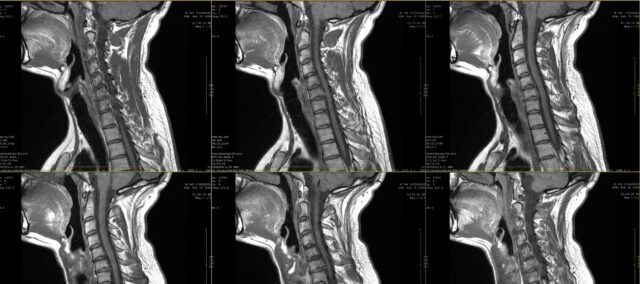

頚椎症性神経根症のレベルを決定する

学校では、神経根痛の痛み止めについて学んだはずだ。 しかし、21世紀の最初の10年間で、橈骨神経痛は必ずしも皮膚分布に沿ったものではないことが明らかになった。 この研究では、患者が描いたradicular pain drawingsの視覚検査とMRIの一致を詳しく調べようとした。実際には、患者が自分の訴えを述べ、それを疼痛描出で補足することが多い。 神経根痛が疑われる場合、多くの場合、罹患している神経根と神経根が侵されている可能性のある範囲を特定するために、医療用画像診断が処方される。 これは多くの場合、日常診療の一部となっているが、これらの痛みの描出と、MRIを用いて決定された罹患神経根との一致がわかるまではわからない。この研究では、Marco et al. (2023)は、radicular pain drawingsとMRI所見を比較した。

頚部神経根症性疼痛の描出とMRI所見との一致を調べるため、本研究では、2ヵ月間持続する疼痛の既往があり、MRIで頚部神経根症と診断された被験者を対象とした。この診断は、臨床情報と放射線科医が評価したMRI所見に基づいて脳神経外科医が行った。